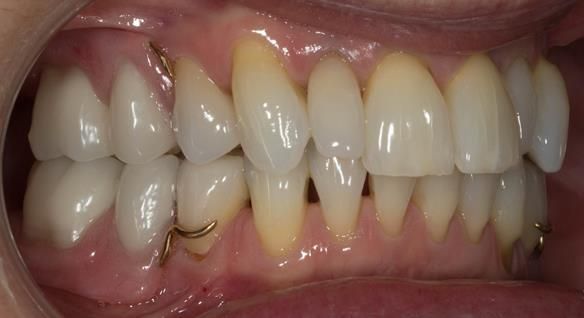

This newsletter describes in step by step detail Angela's transition through immediate partial dentures to crown supported definitive metal based dentures.

This 58 year old woman was referred to me by her general dental practitoner for treatment.

The clinical situation and treatment process is shown in detail below with photographs. I (Finlay Sutton) provided the clinical work and Rowan Garstang provided the technical work.